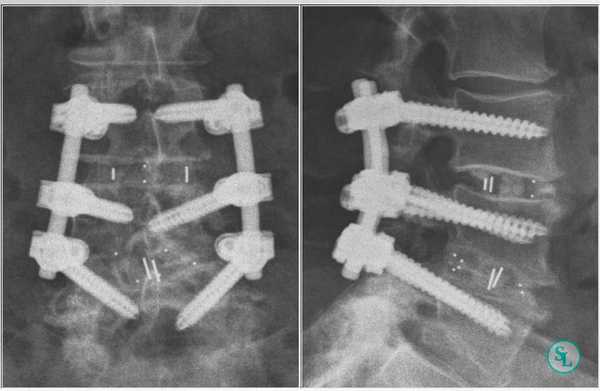

Последний этап транспедикулярной фиксации состоит в создании межтеловой компрессии при помощи специального инструмента и затягивания винтов. На ранее подготовленные декортицированные дуги и поперечные отростки выкладывается алло-или аутотрансплантат. Трансплантат используемый для создания спондилодеза можно смешивать с нативной смесью полученной в результате фильтрации интраоперационного отделяемого во время работы высокоскоростного бора. В конце операции выполняется рентгенологический контроль в 2-х проекциях.

Интраоперационная рентгенография поясничного отдела позвоночника после трансфораминального межтелового спондилодеза.

В день операции пациентам не запрещено сидеть, вставать, ходить. Использование корсета поясничного отдела позвоночника допустимо при многоуровневой стабилизации, при одноуровневом TLIF ношение корсета не требуется. Дренажи удаляются через 48 часов после операции. К более активной реабилитации пациенты приступают через 2 суток после операции, выполняется физиотерапевтическое лечение и лечебная физкультура. На 5-7 сутки с момента операции пациент выписывается и наблюдается амбулаторно. До формирования костного блока, а именно до 3 месяцев, пациентам запрещено поднимать тяжести, выполнять ротационные движения и слишком сильно наклонятся вперед. Через 1, 3 месяцев выполняется контрольная рентгенография уровня хирургического вмешательства в 2-х проекциях.

Сформированный спондилодез на уровне L3-L4.